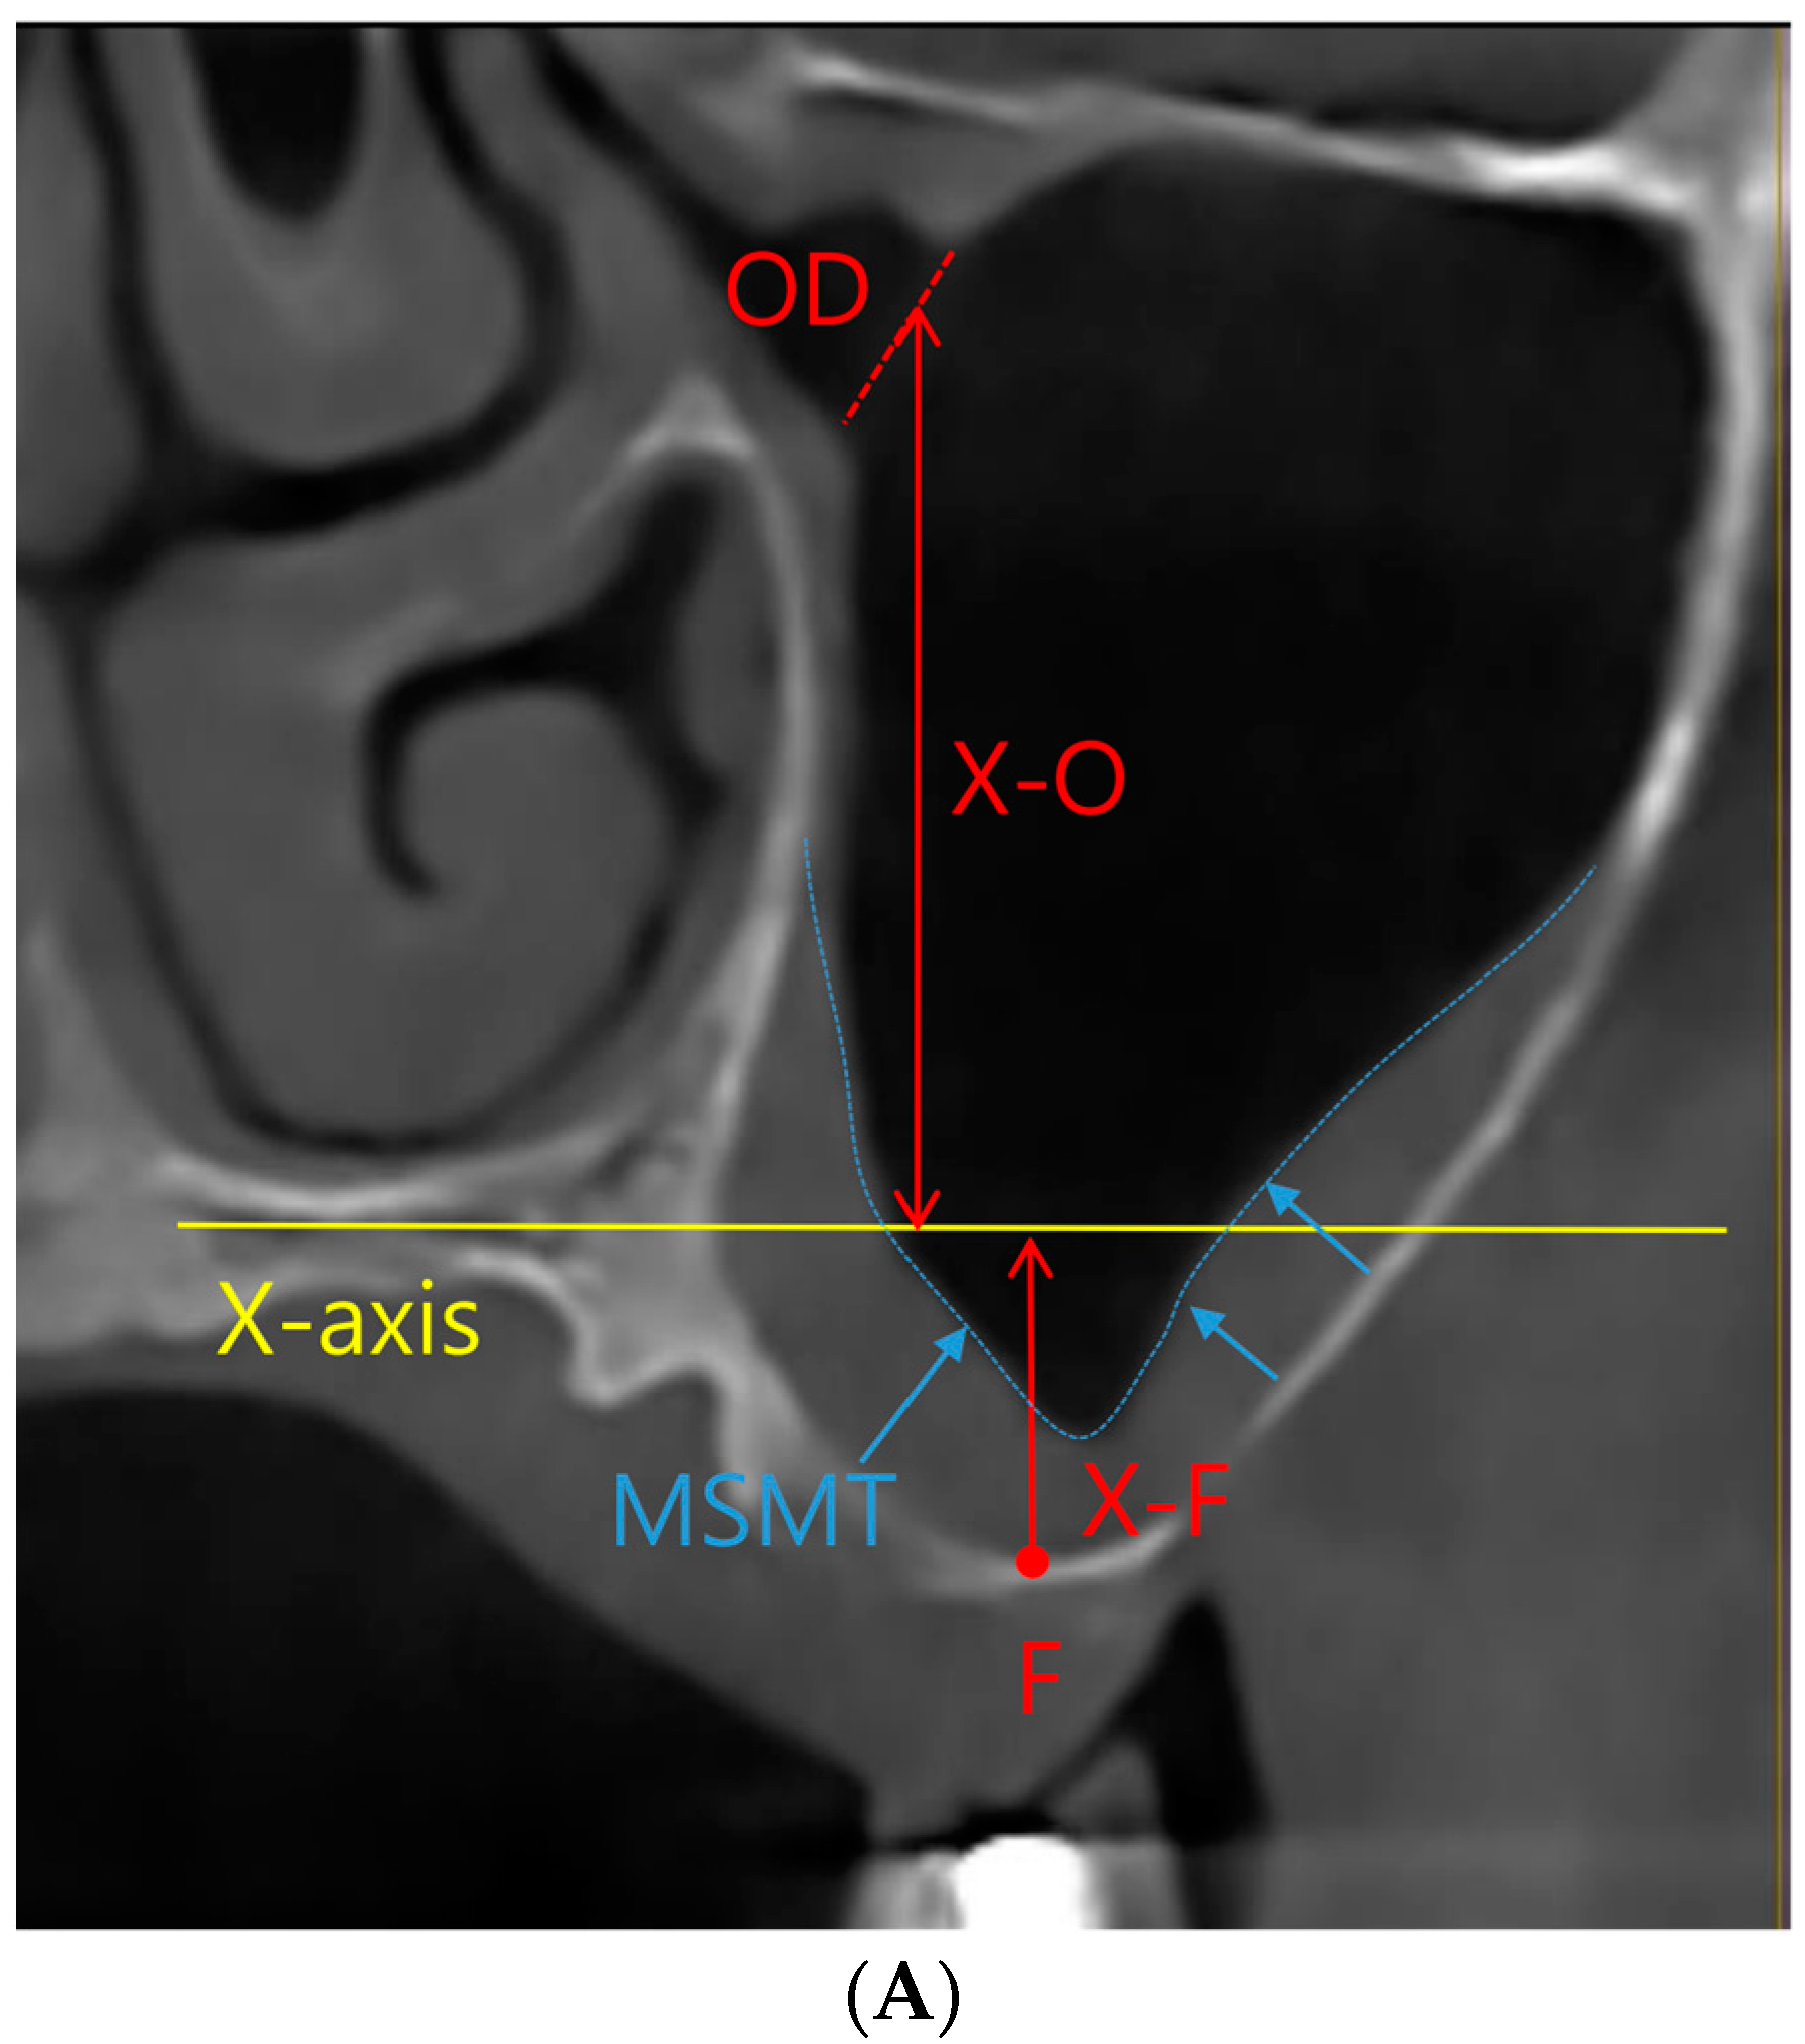

All study participants underwent CBCT imaging both before and after their surgical interventions, with a mean postoperative imaging interval of 7.0 ± 1.8 months. To provide comprehensive procedural descriptions, InVivoDental (Version 6.0.5, Anatomage, San Jose, CA, USA) was employed for acquiring CBCT images. Subsequently, the images were meticulously exported the Digital Imaging and Communications in Medicine (DICOM) files and meticulously loaded them into InVivo software (Version 6.0.5) for precise measurement. Within this software, we ascertained the preoperative and postoperative values for MSMT, MOD, and the ratio of MSMT to MOD (Figure 1).

Figure 1.

Coronal view of cone-beam computed tomographic images of the maxillary sinus. (A) Preoperative view. X-axis, nose floor in coronal view; OD, maxillary sinus ostium diameter; F, the floor of the maxillary sinus; X-F, distance between the X-axis and floor of the maxillary sinus; X-O, distance between the X-axis and maxillary sinus ostium; MSMT, maxillary sinus mucosal thickness; X-F + X-O, maxillary sinus ostium height/distance between the maxillary sinus ostium and sinus floor. (B) Postoperative view of sinus augmentation and bone graft. X-B, distance between the X-axis and sinus augmentation, X-F + X-B, increase in alveolar bone height in sinus augmentation.